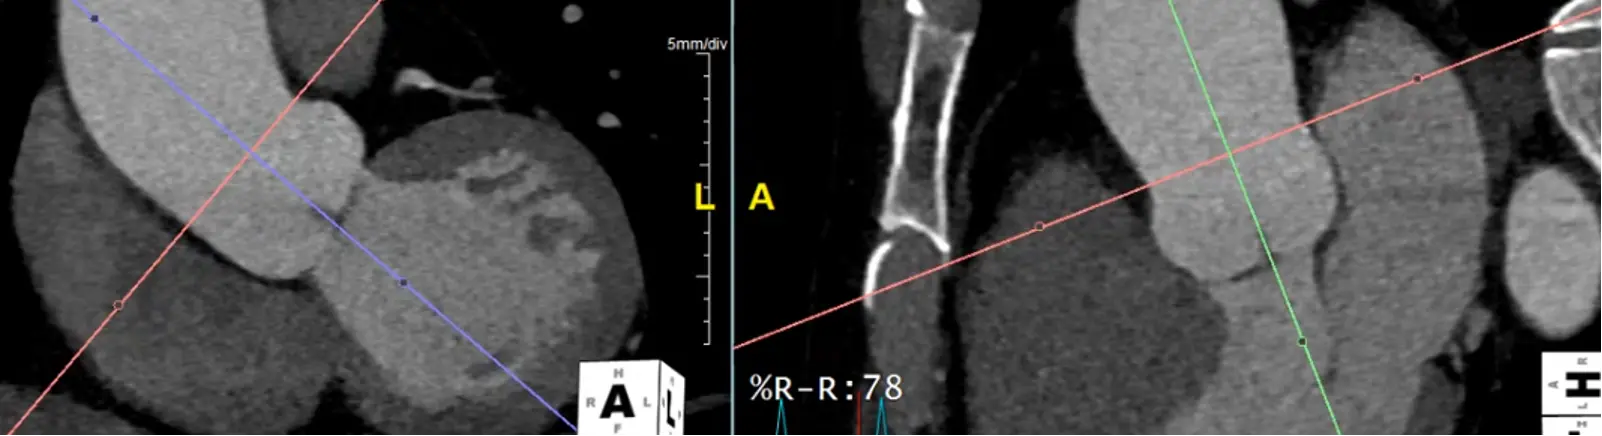

Measure at the widest segment

- The widest segment (typically) is at the mid-aorta at the level of the main pulmonary artery (MPA)

- Same as above, drag your crosshairs to the desired level and adjust to be perpendicular to the artery wall in the coronal and sagittal views. Line up the blue/green line to be in the center/parallel to the long axis of the aorta at that level.

- In the axial view, the âtrue short axisâ should appear like a circle

Alt+Dto auto-measure- Right click and

Captureto add this to theSeries List